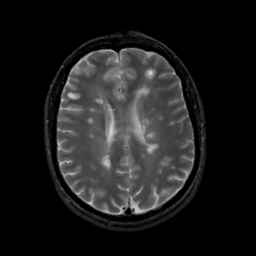

MR Study #12, May 12, 1991 -- Slice #32